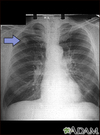

Nucleic-Acid Amplification Test (NAAT): rapid diagnostic test conducted on sputum or urine Microbiology: send three deep cough sputum samples; analyse with Ziehl-Neelsen stain (will turn red) Chest Xray - Latent disease may show Ghon complex Reactivated TB may show patchy or nodular consolidation with cavitation (gas filled spaces in the lungs)

64

what would Disseminated Miliary TB look like on chest xray

**Patchy Consolidation** Ghon Complex Granulomatous Lesions **Hilar Lymphadenopathy** - (enlargement) Pleural Effusion